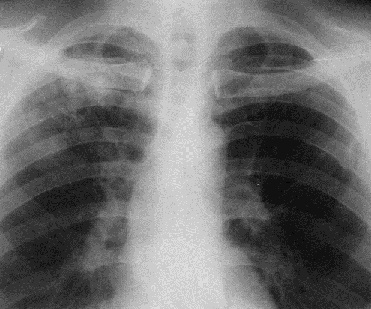

Рис. 2. Рентгенограмма органов грудной полости в прямой проекции. Слева на всем протяжении легочного поля – просветление.

Распространенное просветление встречается при пневмотораксе (рис 2). При этом, как правило, в медиальных отделах видим коллабированное легкое, смещение средостения в противоположный бок, а размещение газа не соответствует долевому строению легкого.